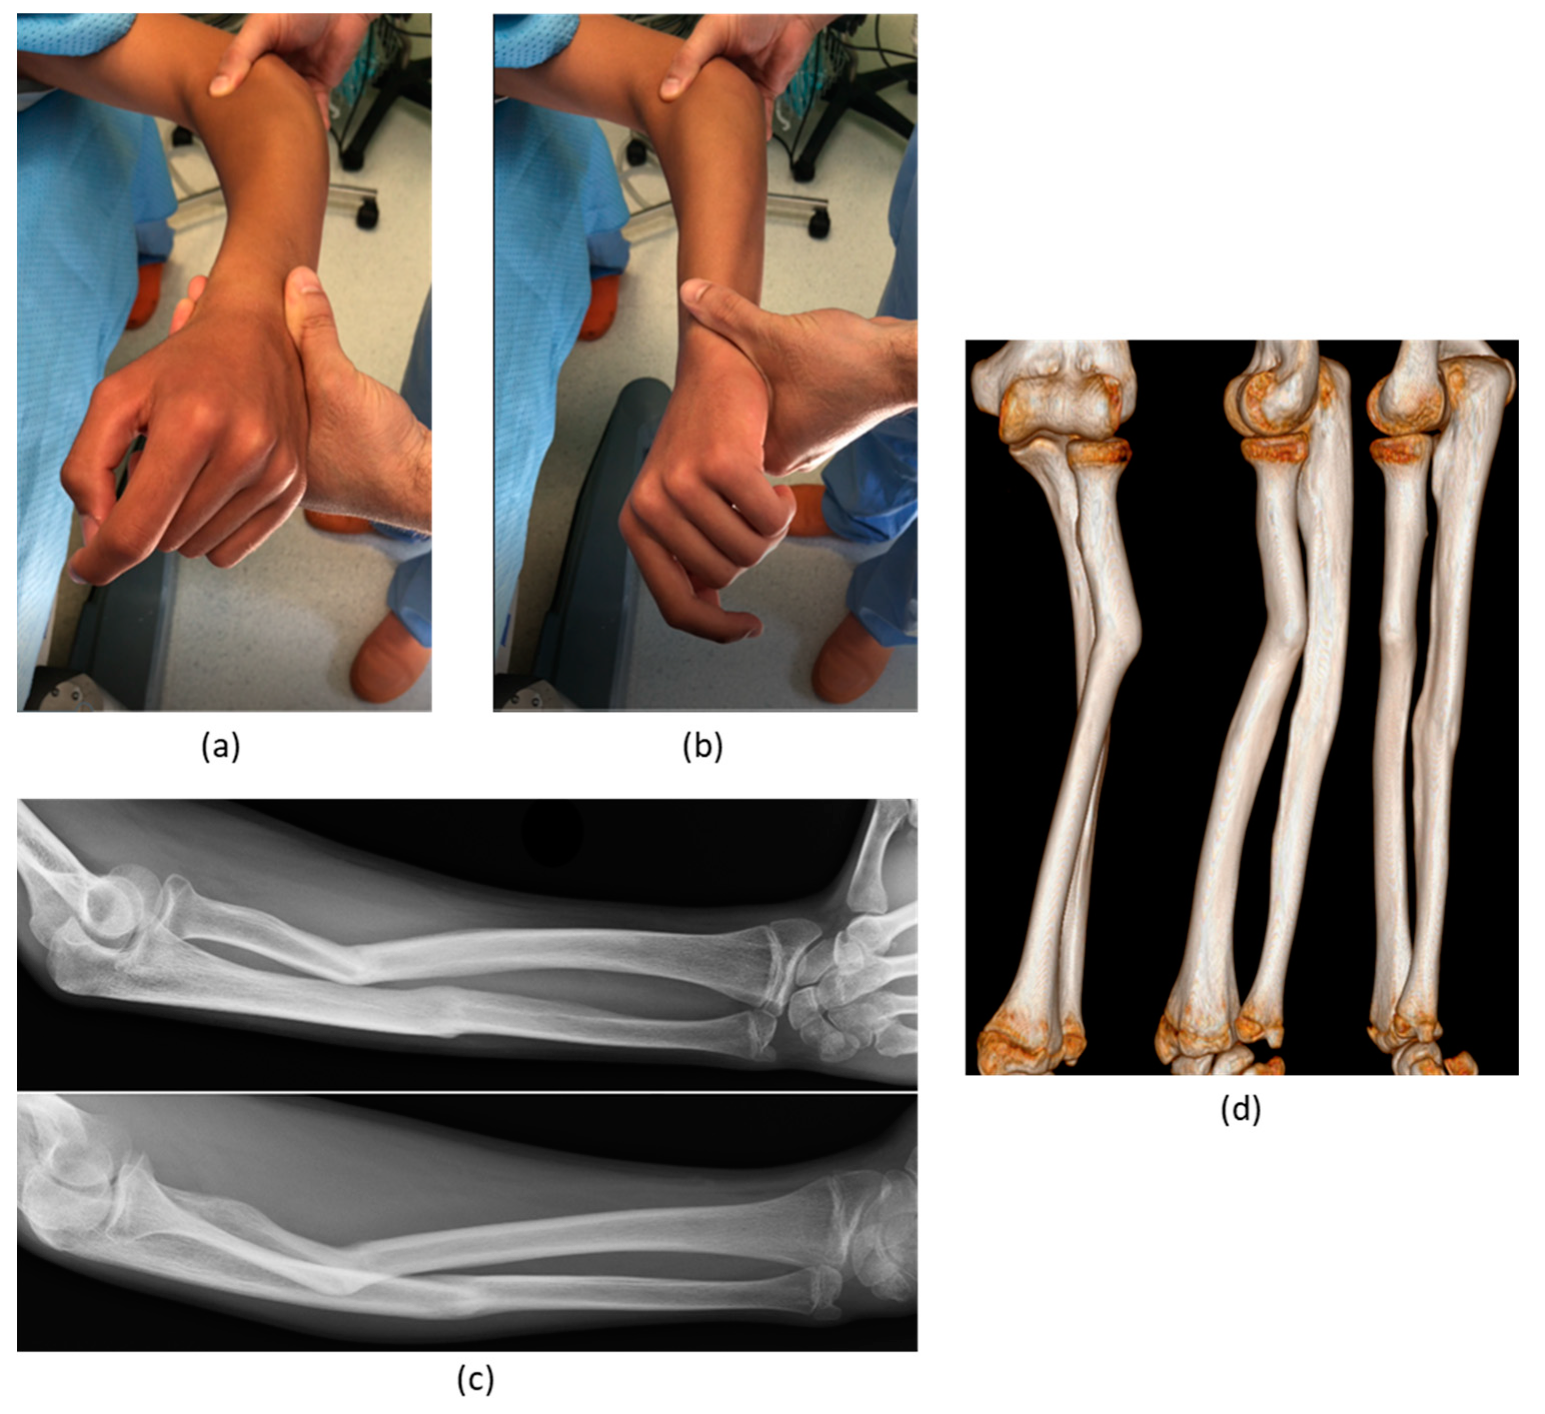

| 2 | M, 13 | Focal fibrocartilagineous dysplasia | Congenital | Bifocal osteotomy stabilized with external fixator | Heterotopic bone formations | Fair (residual dislocation of the radial head with shortening of the ulna) |

| 3 | M, 15 | Post-traumatic forearm malunion deformity | Post-traumatic | Bifocal osteotomy stabilized with 1/3 tubular plate | None | Corrected |